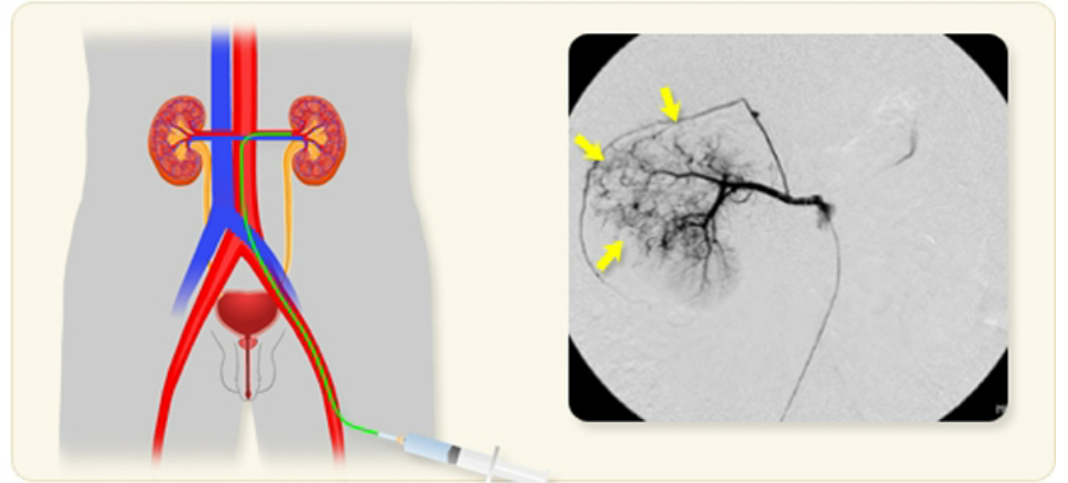

2. 신동맥 색전술 시술 과정

신동맥 색전술은 혈관을 통해 병변 부위에 접근하여 색전 물질을 주입하는 방식으로 진행됩니다. 보통 국소 마취 후 시행합니다. 시술 시간은 질환과 병변의 크기에 따라 30분에서 2시간까지 걸릴 수 있습니다.

- 혈관 접근: 대퇴동맥 또는 요골동맥을 통해 미세 카테터를 삽입합니다.

- 혈관 조영술: 조영제를 주입하여 혈관 상태와 병변 부위를 정확히 파악합니다.

- 색전 물질 주입: 병변 부위로 가는 혈류를 차단하기 위해 적절한 색전 물질을 주입합니다.

- 혈관 폐색 확인: 색전 후 혈류 차단 여부를 재확인하고 필요 시 추가 시술을 진행합니다.